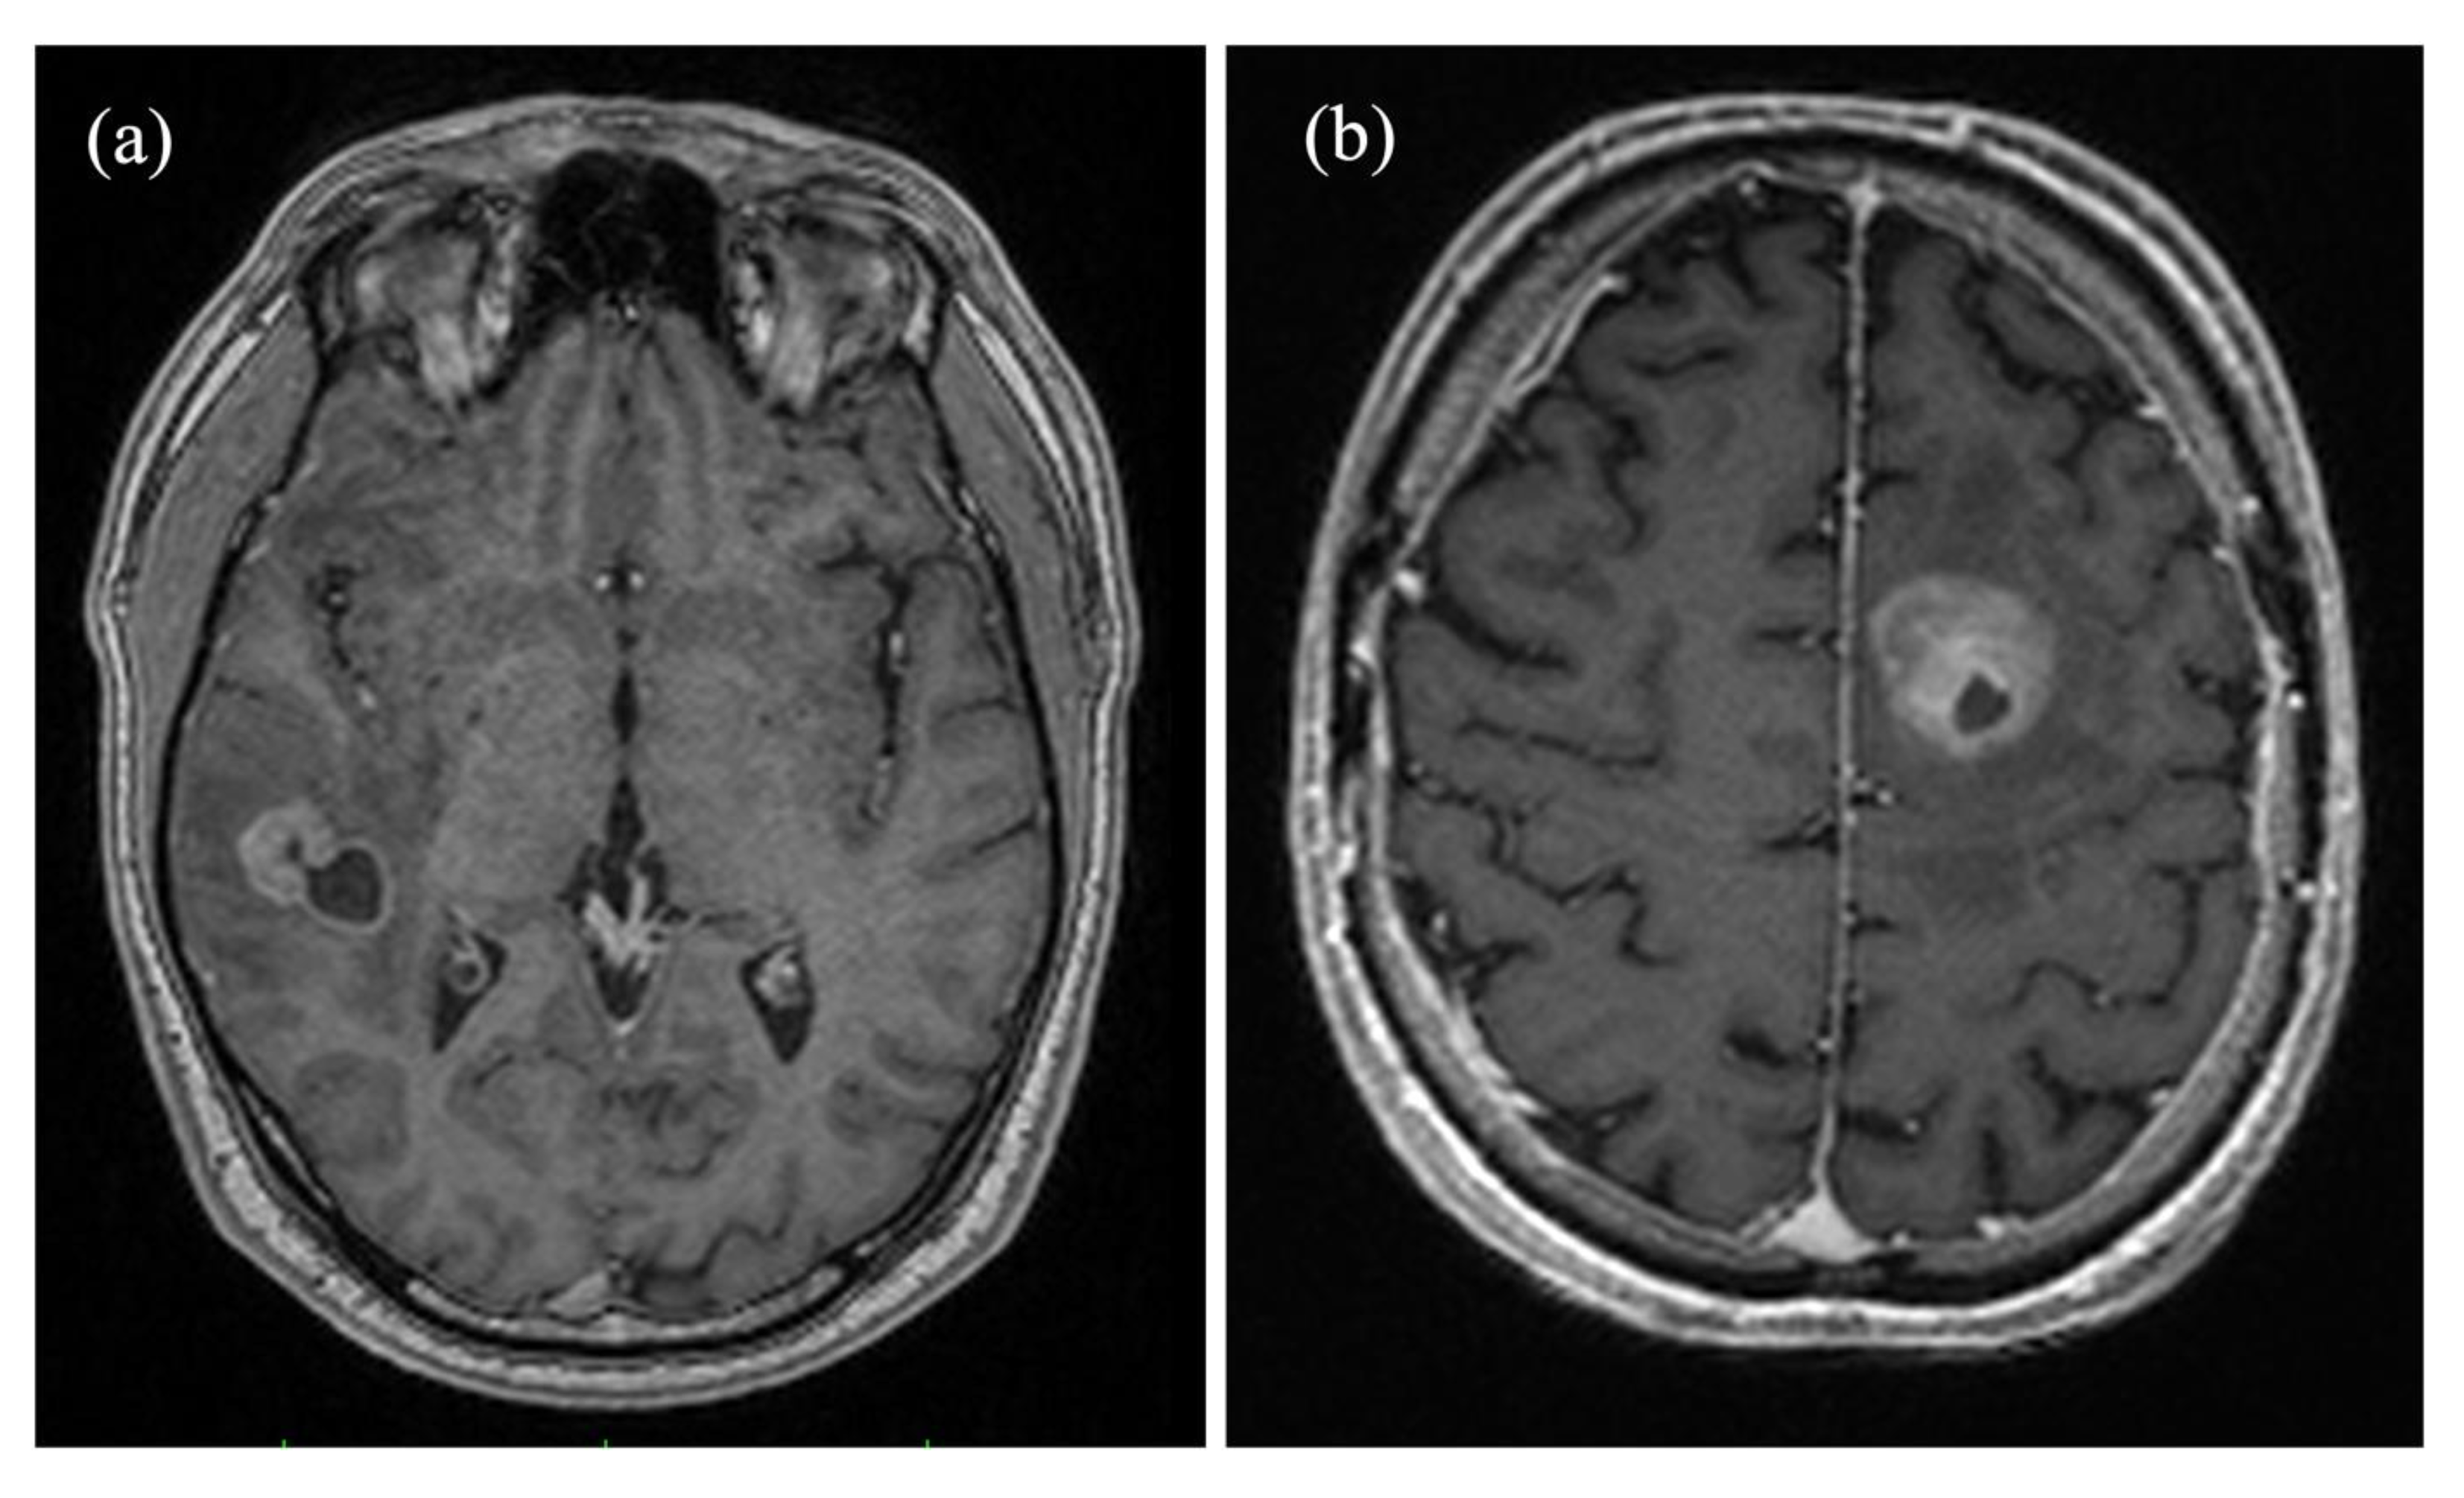

2.3. Image Processing

2.4. Calculation of Perfusion and Oxygenation Parameters

2.5. Artificial Neural Network